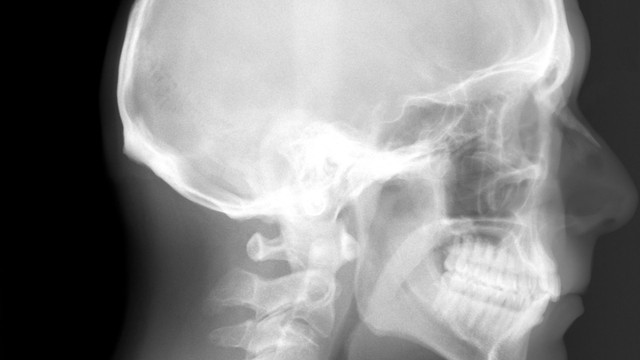

X quang